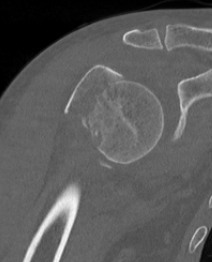

Four part